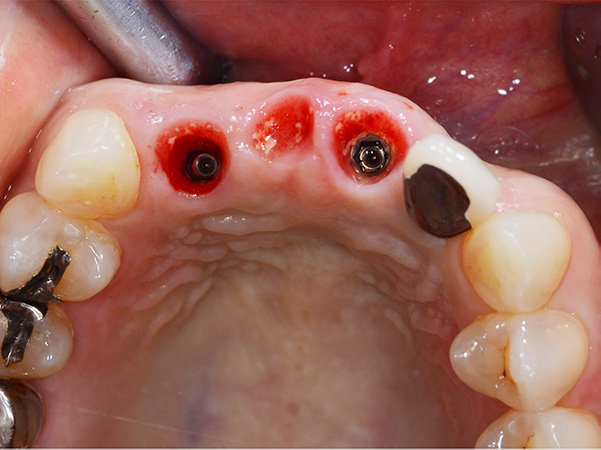

1次手術時の流れ

①手術開始時

②被せ物を外した状態

③抜歯

④サージガイドを使用したインプラント体の埋入

⑤インプラント体を埋入した状態

⑥仮歯を製作していく段階

⑦仮歯を装着した状態

埋入したばかりのインプラント体に負担がかからないように、下の歯と当たらないような形と噛み合わせになるよう調整しています。

手術後2weeks

歯ぐきの腫れもなく、経過は良好でした。

手術後1.5ヶ月

手術直後と比較すると、歯ぐきが少し下がってきていますが、それ以外に変化はありませんでした。

術後4ヶ月 仮歯の調整

1次手術時に製作した仮歯を外し、歯ぐきと周りの歯と調和するように仮歯の形を修正しました。本症例では骨造成を同時に行ったため、唇側の歯ぐきの幅が減ることなく、きれいな状態を保っています。